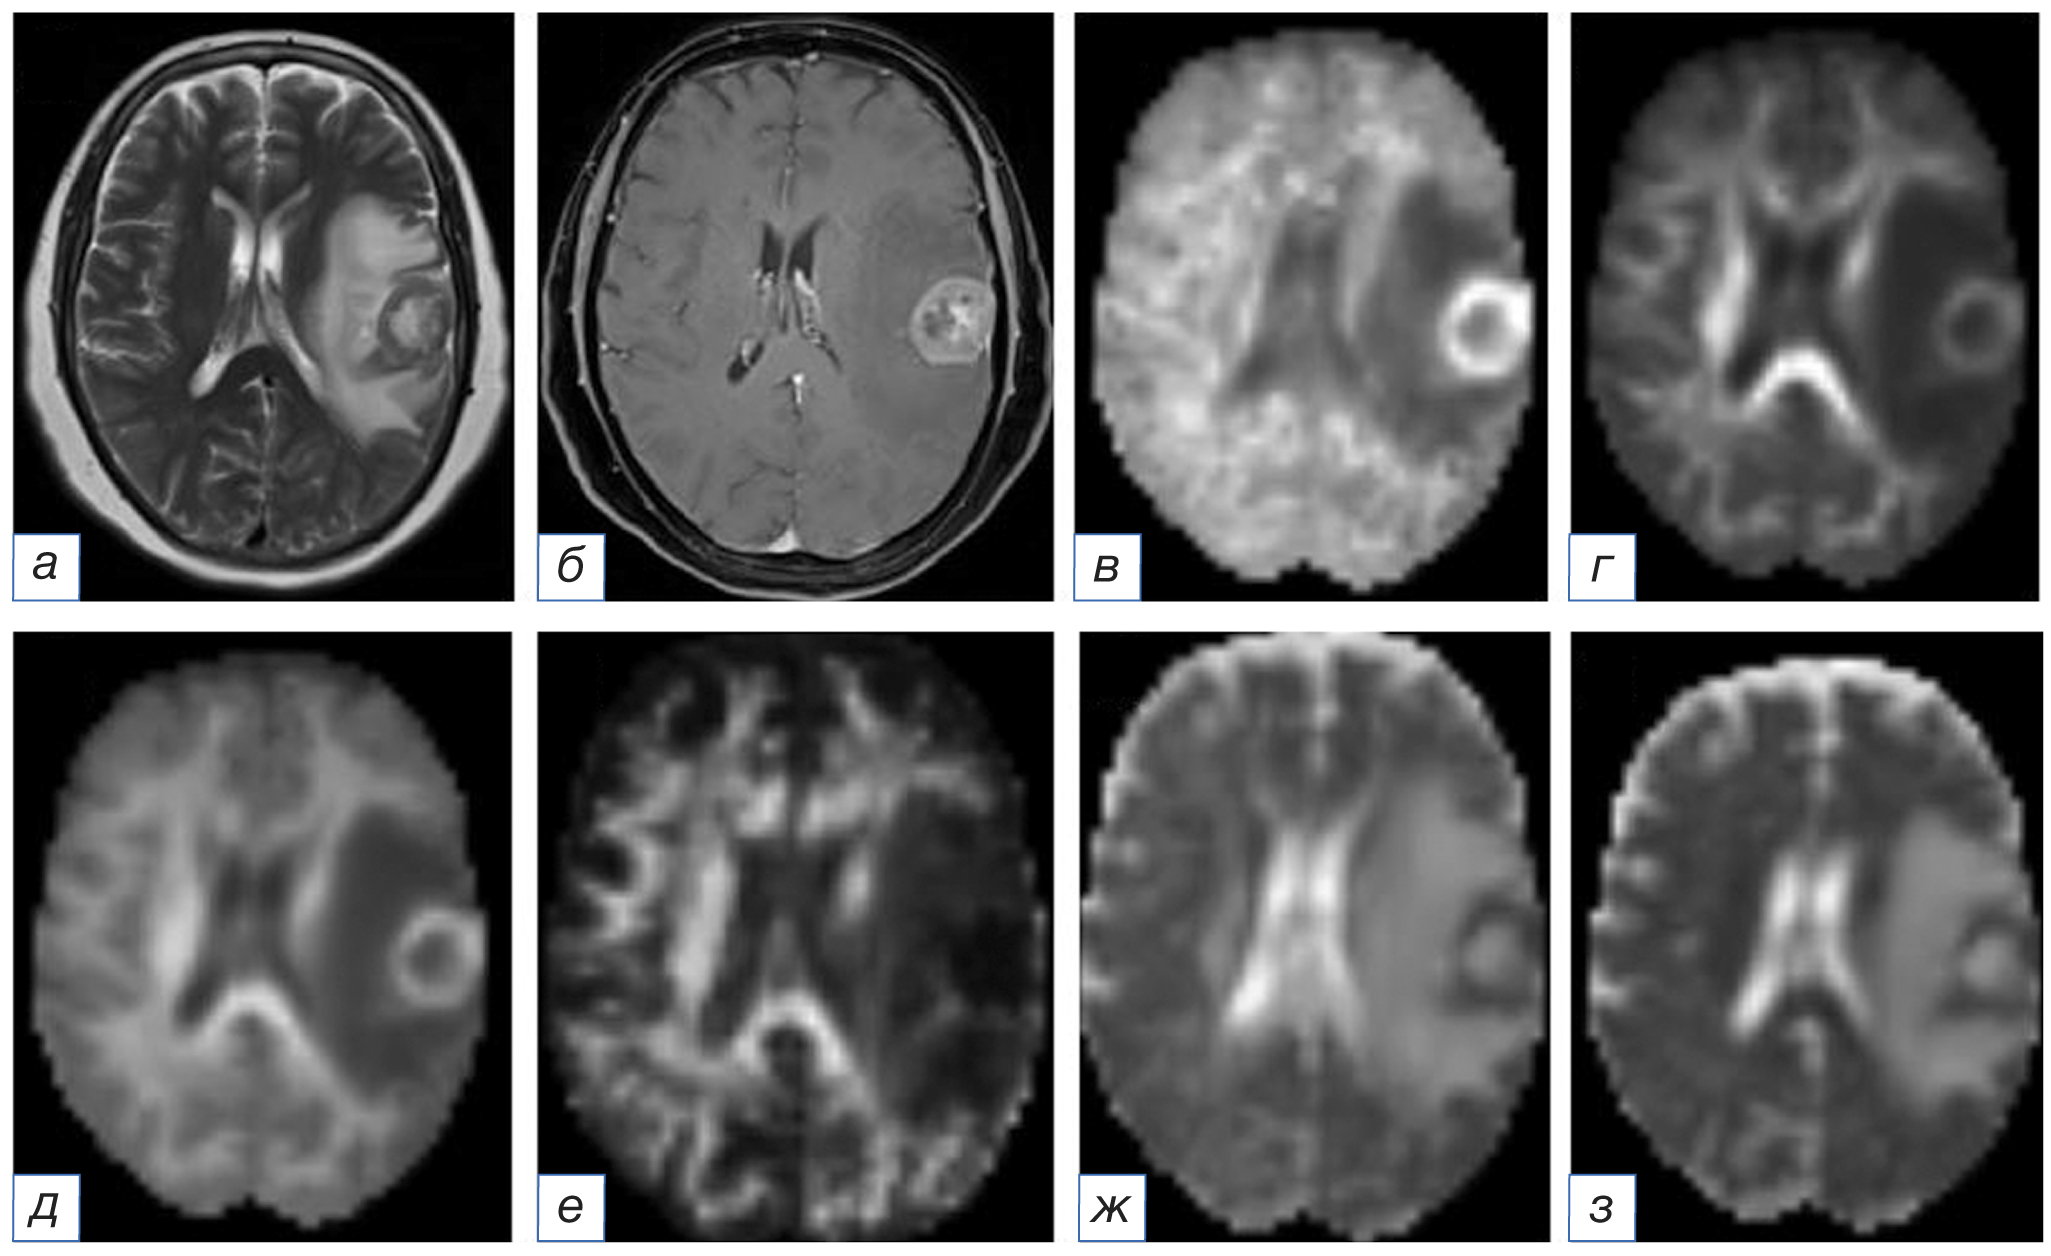

Рис. 3. Магнитно-резонансная томограмма головного мозга: метастаз рака лёгкого в левой лобной доле: а (Т2-WI) — в левой лобной доле определяется образование с центральной полостью некроза без признаков перифокального отёка; б (Т1-WI после внутривенного введения контрастного вещества) — визуализируется умеренное неравномерное накопление контрастного препарата, преимущественно по контуру образования; в (аксиальный куртозис) — в левой лобной доле образование определяется в виде участка гетерогенного МР-сигнала, гипоинтенсивного в центральных отделах; г (радиальный куртозис) — в левой лобной доле образование определяется в виде участка гетерогенного МР-сигнала, гипоинтенсивного в центральных отделах, слабого гиперинтенсивного по периферии; д (средний куртозис) — в левой лобной доле образование определяется в виде участка гетерогенного МР-сигнала, гипоинтенсивного в центральных отделах; е (куртозисная анизотропия) — в левой лобной доле образование определяется в виде участка преимущественно пониженного МР-сигнала; ж (аксиальная диффузия экстрааксональной жидкости) — в левой лобной доле образование определяется в виде участка гетерогенного МР-сигнала, гиперинтенсивного в центральных отделах и слабого гипоинтенсивного по периферии; з (радиальная диффузия экстрааксональной жидкости) — в левой лобной доле образование определяется в виде участка гетерогенного МР-сигнала, гиперинтенсивного в центральных отделах и изоинтенсивного по периферии.